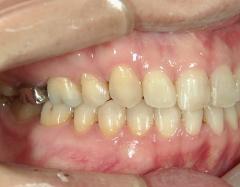

矯正歯科 治療前

全顎ワイヤー矯正 症例(2)

36歳女性 磐田市

在住

治療期間2年6

ヶ月